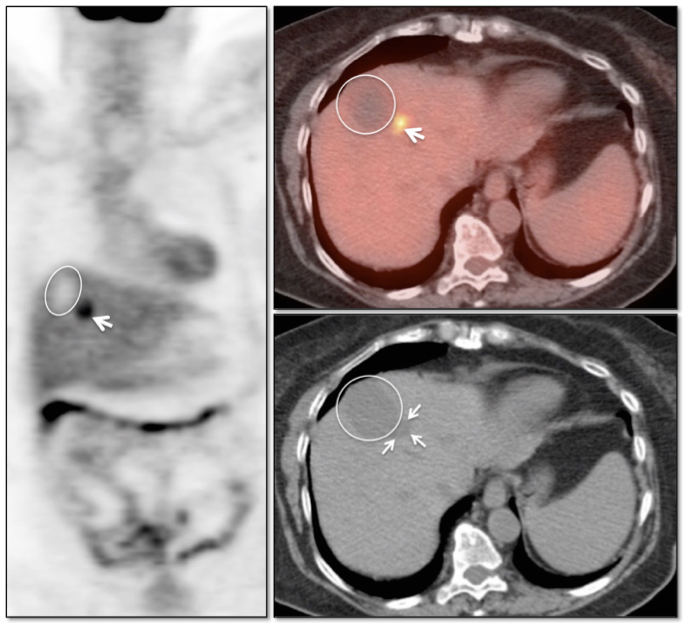

Radiofrequency Ablation of Liver Lesions

Although there is considerable variation in the recommended timing of PET/CT imaging after radiofrequency ablation of liver lesions, PET/CT has shown considerable utility for detecting recurrent/residual disease.

Some advocate post-procedure PET/CT imaging 24-48 hours after ablation to assure that the entire lesion has been fully treated (any remaining FDG uptake at this very early stage should represent residual active tumor, not post-procedural inflammation).

Later follow-up can then often performed, as clinically warranted (often at 3 and 6-months).

Benign Findings:

- Complete absence of metabolic activity in an ablated lesion is consistent with successful treatment.

- A homogeneous rim of well-defined peripheral hypermetabolic activity surrounding a non-avid hypodensity is presumed to represent post-ablation inflammatory changes.

The peripheral nature of this uptake is often best appreciated on the coronal images.

Recurrent/Residual Malignancy:

- Any nodular or focal uptake within or abutting the ablated lesion is highly suspicious for malignancy.